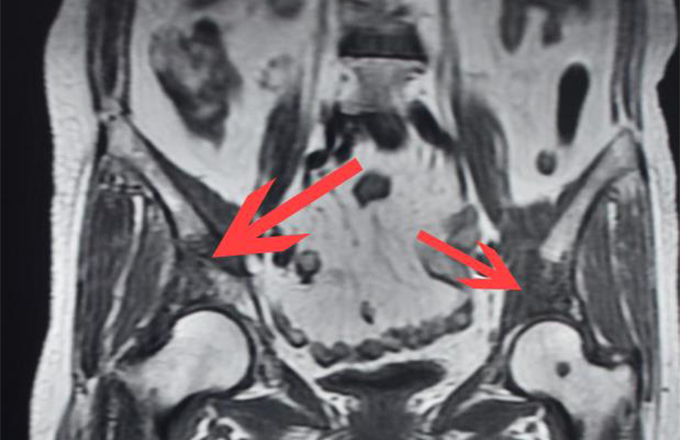

体内骨头被这东西“吃”掉了一大块!持续性疼痛,一定要尽早就医!

本网讯(文化策划中心丁建萍/文)七旬老人的肚子右侧隐隐作痛,本以为忍一忍,这莫名其妙的疼痛过几天就能消失,可是,渐渐地,老人发现只要抬腿迈步,脚就使不上劲,直到后来严重影响行走,到医院检查发现是髋关...2020-09-181663 -